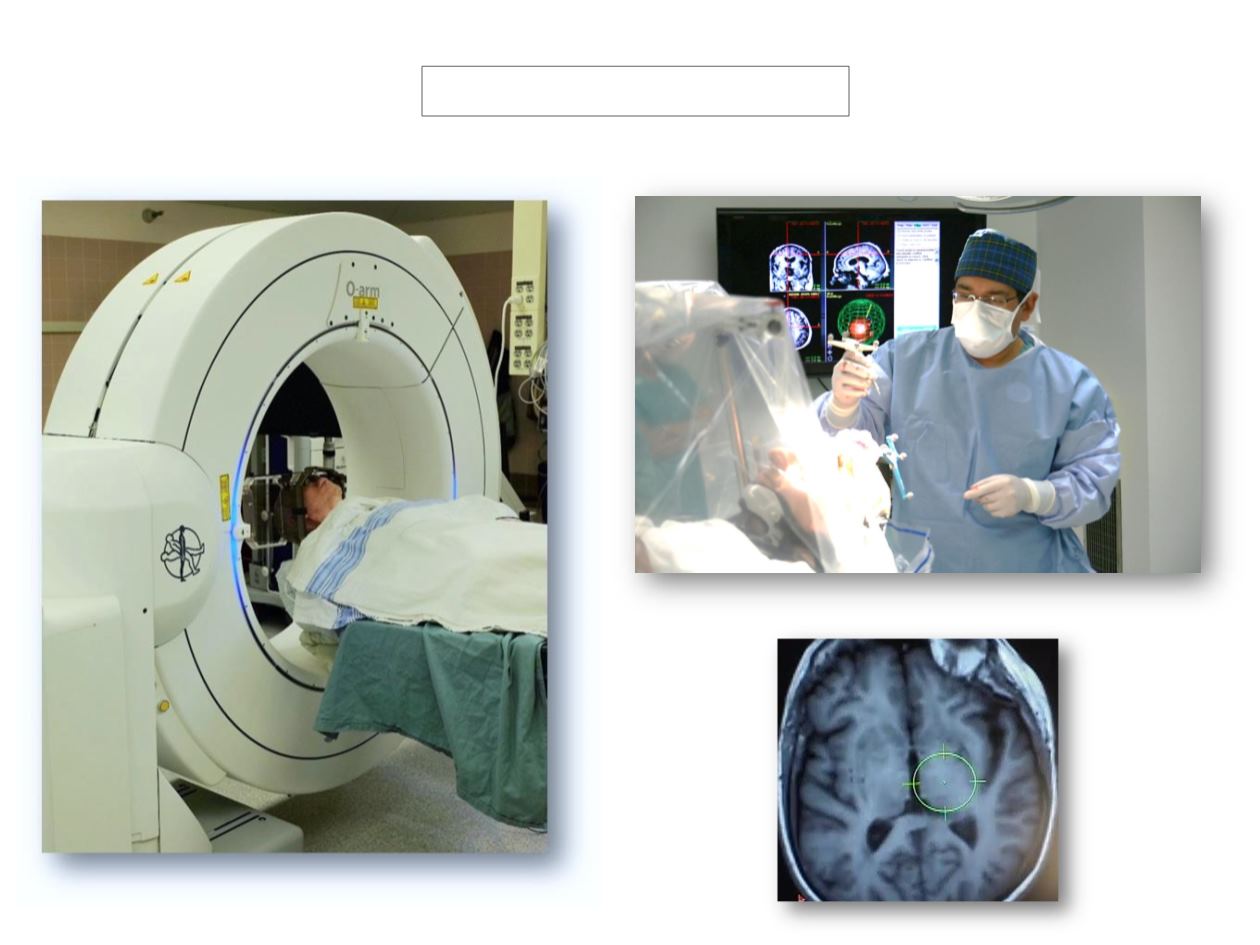

REAL TIME MRI-GUIDED DBS